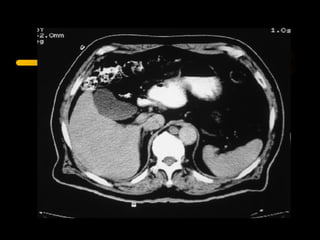

La tomografía computada fue desarrollada por Sir Godfrey Hounsfield y Allan Cormack, quienes recibieron el Premio Nobel de Fisiología o Medicina en 1979 por su trabajo pionero en la aplicación de la computación para generar imágenes transversales del cuerpo humano. La tomografía computada utiliza rayos X y computadoras para crear imágenes transversales del cuerpo.